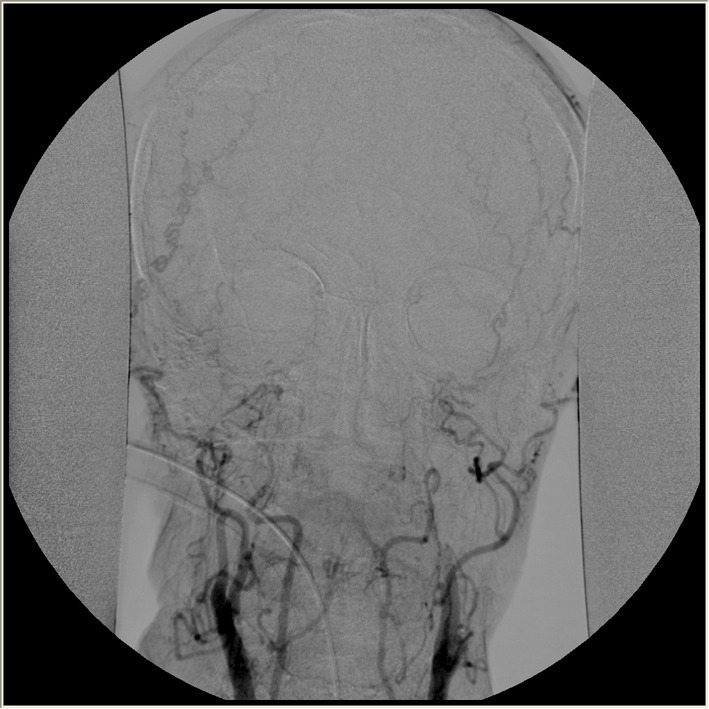

Спустя еще неделю, 22 декабря 2013 по приглашению того же судьи, что дал охранный ордер приходит независимый эксперт — профессор, завотделением детской неврологии очень авторитетного заведения - Школы медицины при Стендфордском университете Paul Graham Fisher. А также родители девочки вызывают известного в стране педиатра Paul A. Byrne, который по странному стечению обстоятельств поддерживает идею, что смерть мозга не является смертью всего организма. Они подтверждают смерть мозга. На энцефалограмме прямые линии, на ангиограмме кровообращения нет ни в одном из отделов мозга, пациентка даже не пытается дышать при отключении ИВЛ. И 24 декабря Суд признает девочку официально покойной и постановляет отключить уже тело от систем жизнеобеспечения, как только истечет охранный ордер от предыдущих юристов.

Июль 2014. У девочки, которой уже исполнилось 13 лет, начинаются регулярные менструации. Тут всем уже становится интересно: для этого гипоталамус должен работать и вырабатывать определенные гормоны. Энцефалограмма и ангиограмма по-прежнему показывают смерть всех отделов мозга.